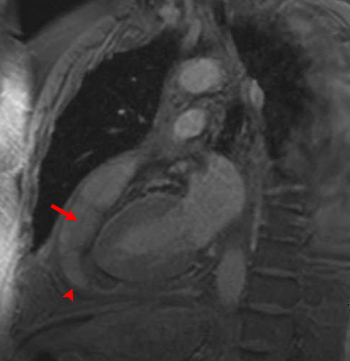

The two chamber long axis T1-weigted fat saturated gradient echo image demonstrates effusive constrictive pericarditis. Notice the septated pericardial effusion (arrow) and the thickened pericardium (arrowhead).